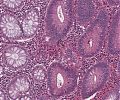

A69 Tubuläres Adenom (Kolon)

Nebeneinander normaler Kolondrüsen und adenomatöser Drüsen.

-

A69 Tubuläres Adenom (Kolon)

Tubuläre Drüsenbildung mit geringen Epithelatypien und einzelnen noch erhaltenen Becherzellen.